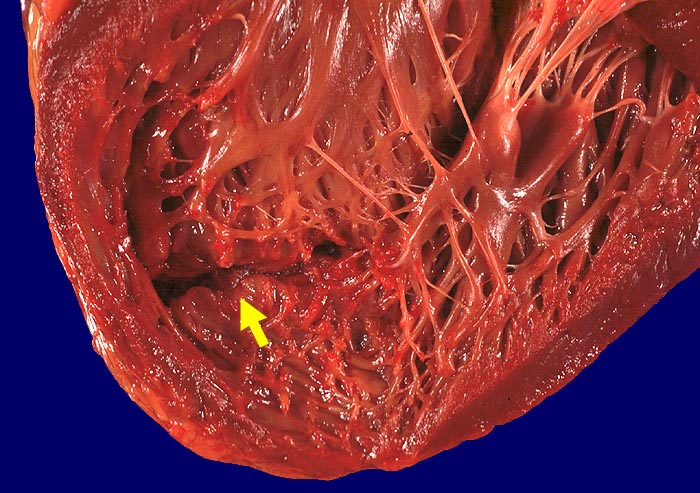

Subakuter Myokardinfarkt des Septums mit Septumruptur

Schlitzförmige Ruptur im Herzseptum.

Subakuter Myokardinfarkt des Septums. Ruptur in den rechten Ventrikel.